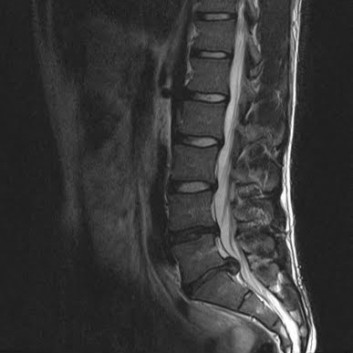

급성 디스크 손상 및 디스크 탈출증

허리 디스크에 의한 급성 통증 발생 시에도 심부신경 주사치료를 통해 효과적으로 통증을 조절 할 수 있습니다. 갑작스런 자극에 의한 신경의 통각 과민을 예방하고 붓고 파열 된 디스크의 크기를 줄임으로써 수술 없이 안전하게 치료가 가능합니다. 효과적인 치료를 위해 반복해서 치료 해야 합니다. 심각한 디스크의 파열은 수술이 필요 할 수도 있습니다.

척추관 협착증의 치료

좁아진 척추관에 의해 발생한 협착증은 심한 경우 주사로 좁아진 공간을 넓게 할 수 없습니다. 다만 심부신경주사치료를 통해 척추관을 효과적으로 감압 할 수 있으며 신경에 대한 주변 조직의 압박을 줄이고 자극과 유착을 제거 합니다. 주사로 해결 되지 않는 경우 신경성형술 등의 시술을 고려 할 수 있으며 운동신경손상 및 통증 정도에 따라 수술을 시행 해야 하기도 합니다.